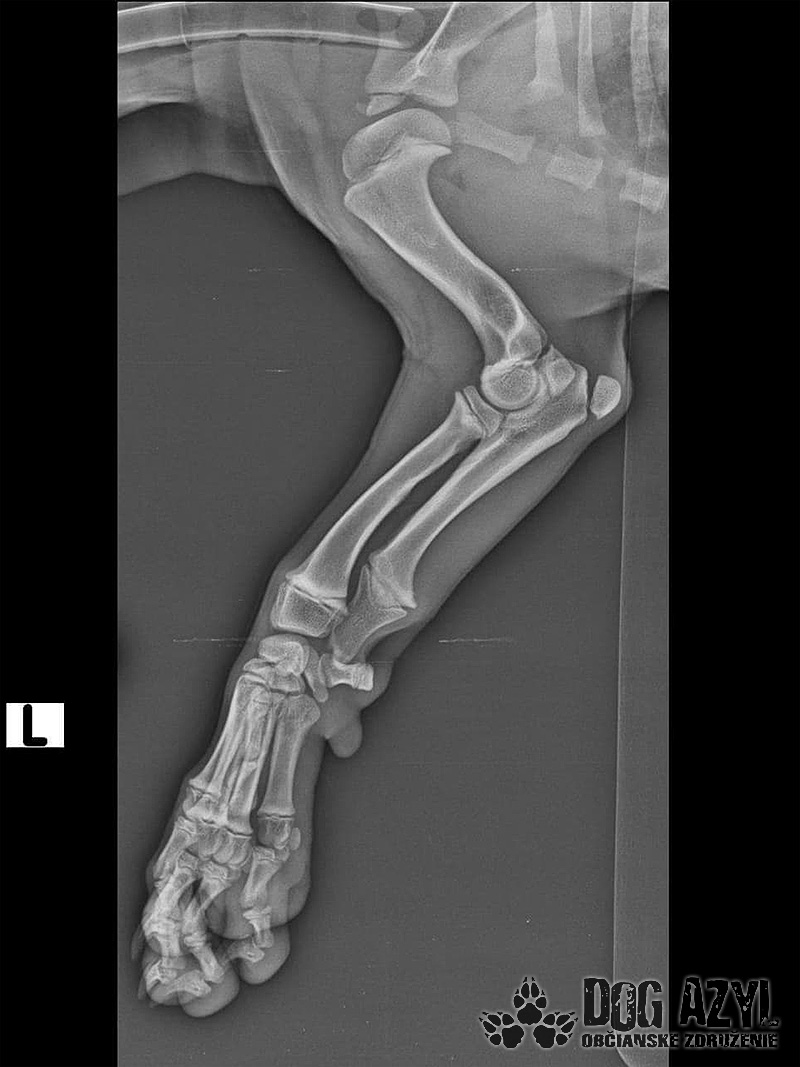

Pluto dnes absolvoval druhú operáciu. Vyberala sa platnička a veľká skrutka, ktorá sa nahradila menším pinom. Koncom mesiaca ho čaká ďalšia a dúfame, že už posledná operácia. Také malinké šteniatko a už toľko bolesti musí prežívať :( Má sa dobre, rastie do krásy a už sa pomaly može naplno šantiť so svojim kamošom v dočasnej opatere. :) Veľmi pekne prosíme, pomôžte nám s úhradou faktúr. Faktúry nájdete priebežne v galérii a na konci článku aj zoznam darcov s prijatou aj chýbajúcou sumou. Po poslednej operácii čakajú Pluta ešte mesiace rehabilitácie, aby sa nožička úplne rozhýbala a mohol ju používať naplno :)

Odoberal sa od drogovo závislých asociálov, ktorý boli vysťahovaný z domu. Ihly, striekačky, ľudské výkaly, rôzne neidentifikovateľné zvratky, špinavé oblečenie, použité kondómy - to všetko nahádzané na jednu kopu v obývačke, kde Pluto so svojou maminkou Miou žili. :( Nevieme ako sa to stalo, kto mu ublížil, ale Pluto má prestrelenú prednú nohu! Viete si predstaviť toho psychicky narušeného človeka, ktorý strieľa na malé bezbranné šteniatko? V dôsledku strelnej rany má doslova rozdrvenú lakťovú kosť. Mali sme veľké obavy, že o nožičku príde, ale MVDr. Vatolík s teamom veterinárnej kliniky Sibra centrum opäť urobil zázrak a malému nožičku napravil a prognóza je viac než dobrá. Čaká ho ešte dlhá cesta k zotaveniu, ale je to odvážny a statočný bojovník. Nechceme si ani len predstaviť čím všetkým si tie zvieratká muesli prejsť, a kto vie koľko ich pôvodne bolo.. Nikto nevie ako a kde skončili Plutovi súrodenci...